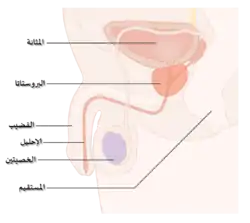

الميكانيكية (الآلية) المرضية

البروستات هي جزء من أجزاء الجهاز التناسلي الذكري، والتي تساعد في تكوين وتخزين السائل المنوي عند الذكر البالغ. تكون البروستات بطول 3 سم تقريباً وتزن ما يقارب 20 غراماً.[58] تقع البروستات في منطقة الحوض تحت المثانة وأمام القناة الشرجية. تحيط القناة بجزءٍ من الإحليل، وهو الأنبوب الذي ينقل البول من المثانة أثناء عملية التبول، ويحمل السائل المنوي أثناء عميلة القذف،[59] وبسبب موقعها هذا فإن أمراض البروستات تؤثر على عملية التبول والقذف وفي حالاتٍ نادرةٍ على عملية التغوط. تحتوي البروستات على العديد من الغدد الصغيرة والتي تساهم في تكوين 20% من السائل الموجود في السائل المنوي الذكري.[60] في سرطان البروستات، تتحول خلايا البروستات الغددية إلى خلايا سرطانية. تحتاج الغدد البروستاتية للهرمونات الذكرية المعروفة بالأندروجينات للعمل بشكل صحيح، والأندروجينات تتكون من التستوستيرون (بالإنجليزية: Testosterone) الذي يُصنَع في الخصيتين، والديهايدروابندروستيرون (بالإنجليزية: dehydroepiandrosteron) الذي يُصنَع من الغدد الكظرية، والديهايدروتيستوستيرون (بالإنجليزية: dihydrotestosterone) والذي يتحول من التستوستيرون (Testosterone) في البروستات نفسها. وأما الأندروجينات فهي مسؤلة عن الصفات الجنسية الثانوية، كظهور شعر الوجه وزيادة الكتلة العضلية للجسم.